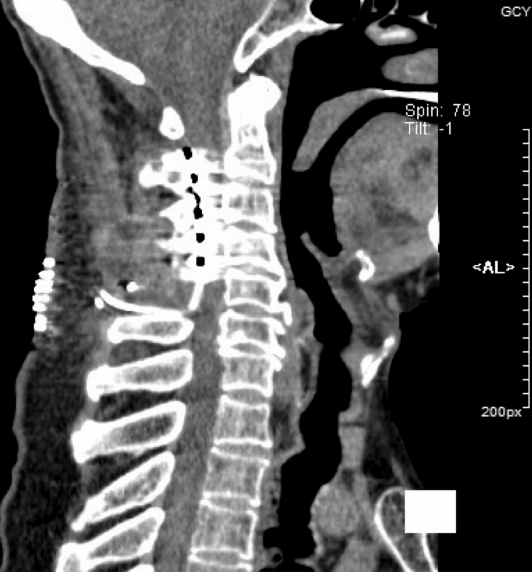

脊髓电刺激术(SCS)

通过全面的评估,拟行脊髓电刺激术(SCS)来缓解疼痛。全麻,在C2-C4节段植入5-6-5片状电极。使用外部刺激器进行测试,VAS评分降低到6分,患者自述“血流回到指尖的感觉”。随后植入了一个永久性刺激器(刺激参数:幅度:1.8mA;脉宽:200µs;频率:40Hz;周期:开900s,关600s)。术后,患者VAS评分降低到5分,PHQ-9评分13分,ODI评分42分。术后9个月随访,VAS评分为4分。

图片